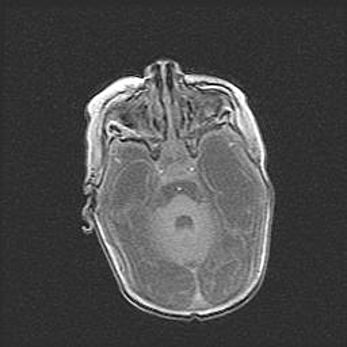

Аномалия Денди-Уокера. Признаки гипоплазии мозолистого тела.

Возраст: 5 месяцев 3 дня

Вес: 5550 г

Пол: мужской

Окружность головы: 39 см

Срок гестации: 40 недель

Аномалия Денди-Уокера – это порок развития головного мозга, для которого характерна триада симптомов: гипотрофия или аплазия червя мозжечка и/или полушарий мозжечка, расширение четвёртого желудочка с формированием ликворной кисты задней черепной ямки, гипертензионная гидроцефалия различной степени.

Гипоплазия мозолистого тела относится к дефектам внутриутробного этапа развития мозговой ткани, возникающим в процессе закладки структур головного мозга, что происходит на начальных этапах развития эмбриона.